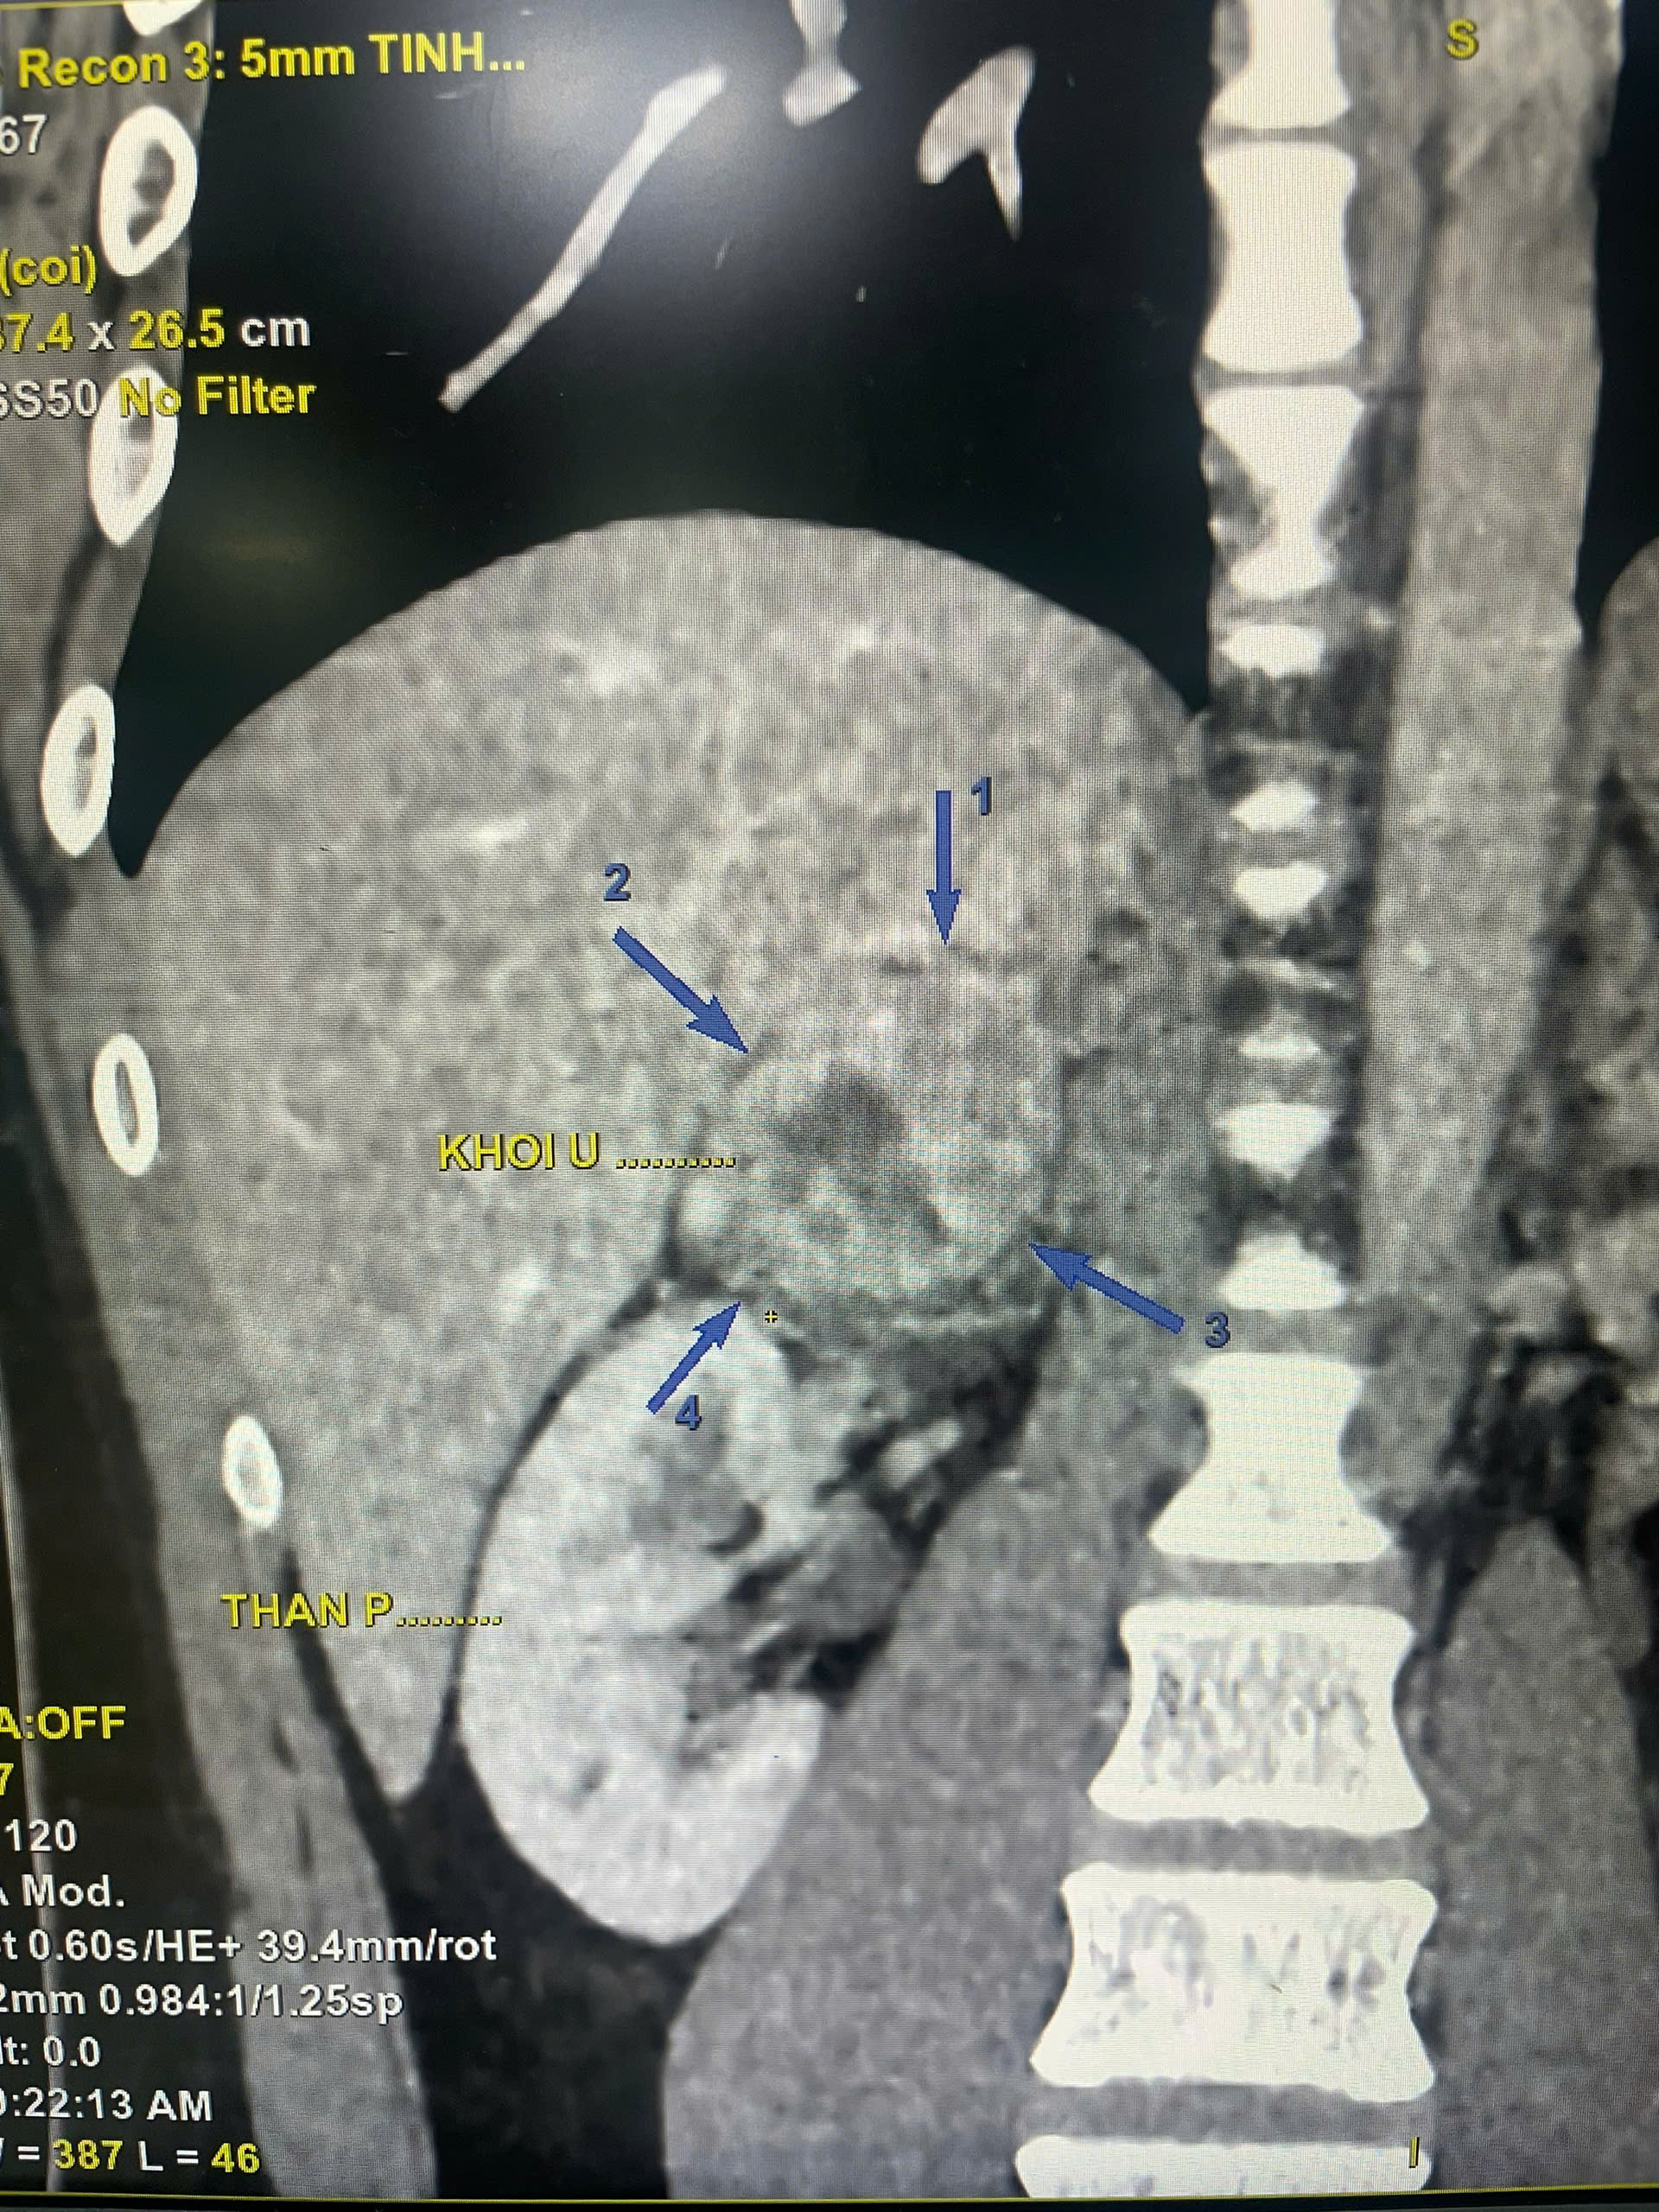

Bác sĩ đã chỉ định chụp CT-Scanner ổ bụng có tiêm thuốc, nhằm loại trừ các tổn thương tiềm ẩn. Kết quả cho thấy:

+ Khối đặc vùng thượng thận phải kích thước 58 × 52 × 44 mm

+ Nhiều hạch ổ bụng chưa loại trừ lymphoma

Hình ảnh kết quả CT- Scaner của người bệnh

Nhờ chất lượng hình ảnh sắc nét của hệ thống CT hiện đại cùng quy trình đánh giá nhanh chóng tại BVĐK Hà Đông, bác sĩ đã kịp thời đưa ra hướng xử trí chuyên môn, giúp bệnh nhân tránh được nguy cơ chậm trễ trong chẩn đoán.